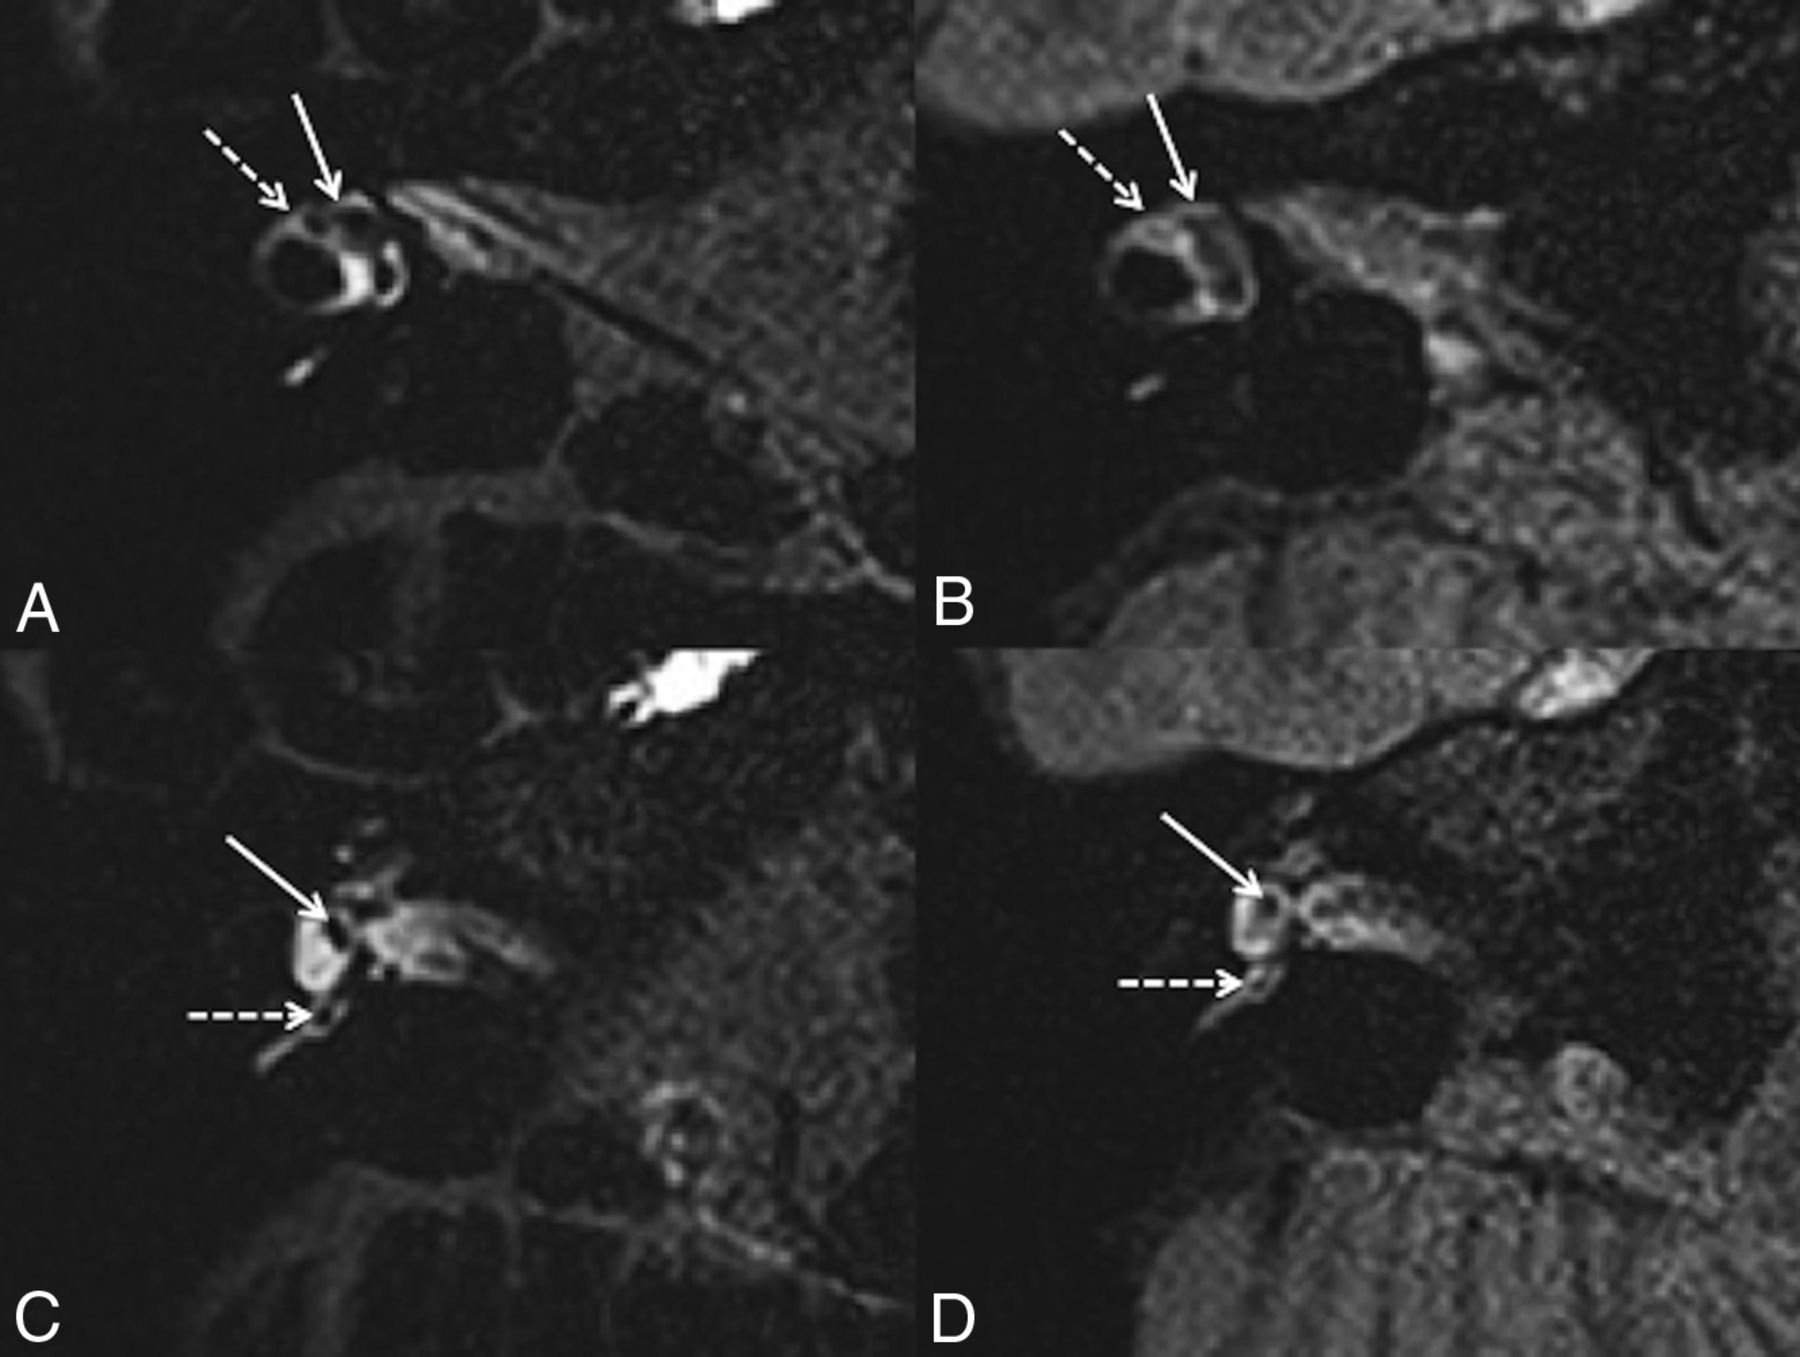

We verified the presence of the following structures (Fig 1): 1) the saccule, an area of hypointense signal located at the medial and anterior walls of the vestibule at the level of the oval window;19,20 2) the utricle, an elliptic area of hypointense signal located in the superior part of the vestibule at the level of the lateral semicircular canal;19,20 and 3) the ampulla of each semicircular canal, an area of hypointense signal surrounded by perilymphatic fluid.

A 42-year-old woman with right possible MD. Axial 3D-FLAIR CFA at the level of the lateral semicircular canal (A) shows a normal utricle (white arrow) and lateral ampulla (right dotted arrow). C, Axial 3D-FLAIR CFA through the inferior part of the vestibule shows a normal saccule (white arrow) and posterior ampulla (white dotted arrow). Axial 3D-FLAIR heavily-T2 VFA at the level of the lateral semicircular canal (B) shows a normal utricle (white arrow), while the lateral ampulla (right dotted arrow) is barely visible. D, Axial 3D-FLAIR heavily-T2 VFA through the inferior part of the vestibule shows a normal saccule (white arrow) and posterior ampulla (white dotted arrow).